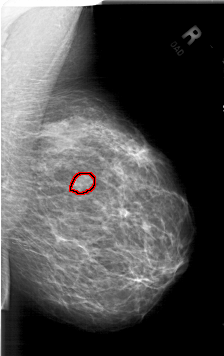

A_1779_1.RIGHT_CC

RIGHT_CC LINES 6331 PIXELS_PER_LINE 4036 BITS_PER_PIXEL 12 RESOLUTION 43.5 OVERLAY

FILE: A_1779_1.RIGHT_CC.OVERLAY

TOTAL_ABNORMALITIES 1

ABNORMALITY 1

LESION_TYPE MASS SHAPE LOBULATED MARGINS ILL_DEFINED

ASSESSMENT 4

SUBTLETY 3

PATHOLOGY BENIGN

TOTAL_OUTLINES 1

BOUNDARY